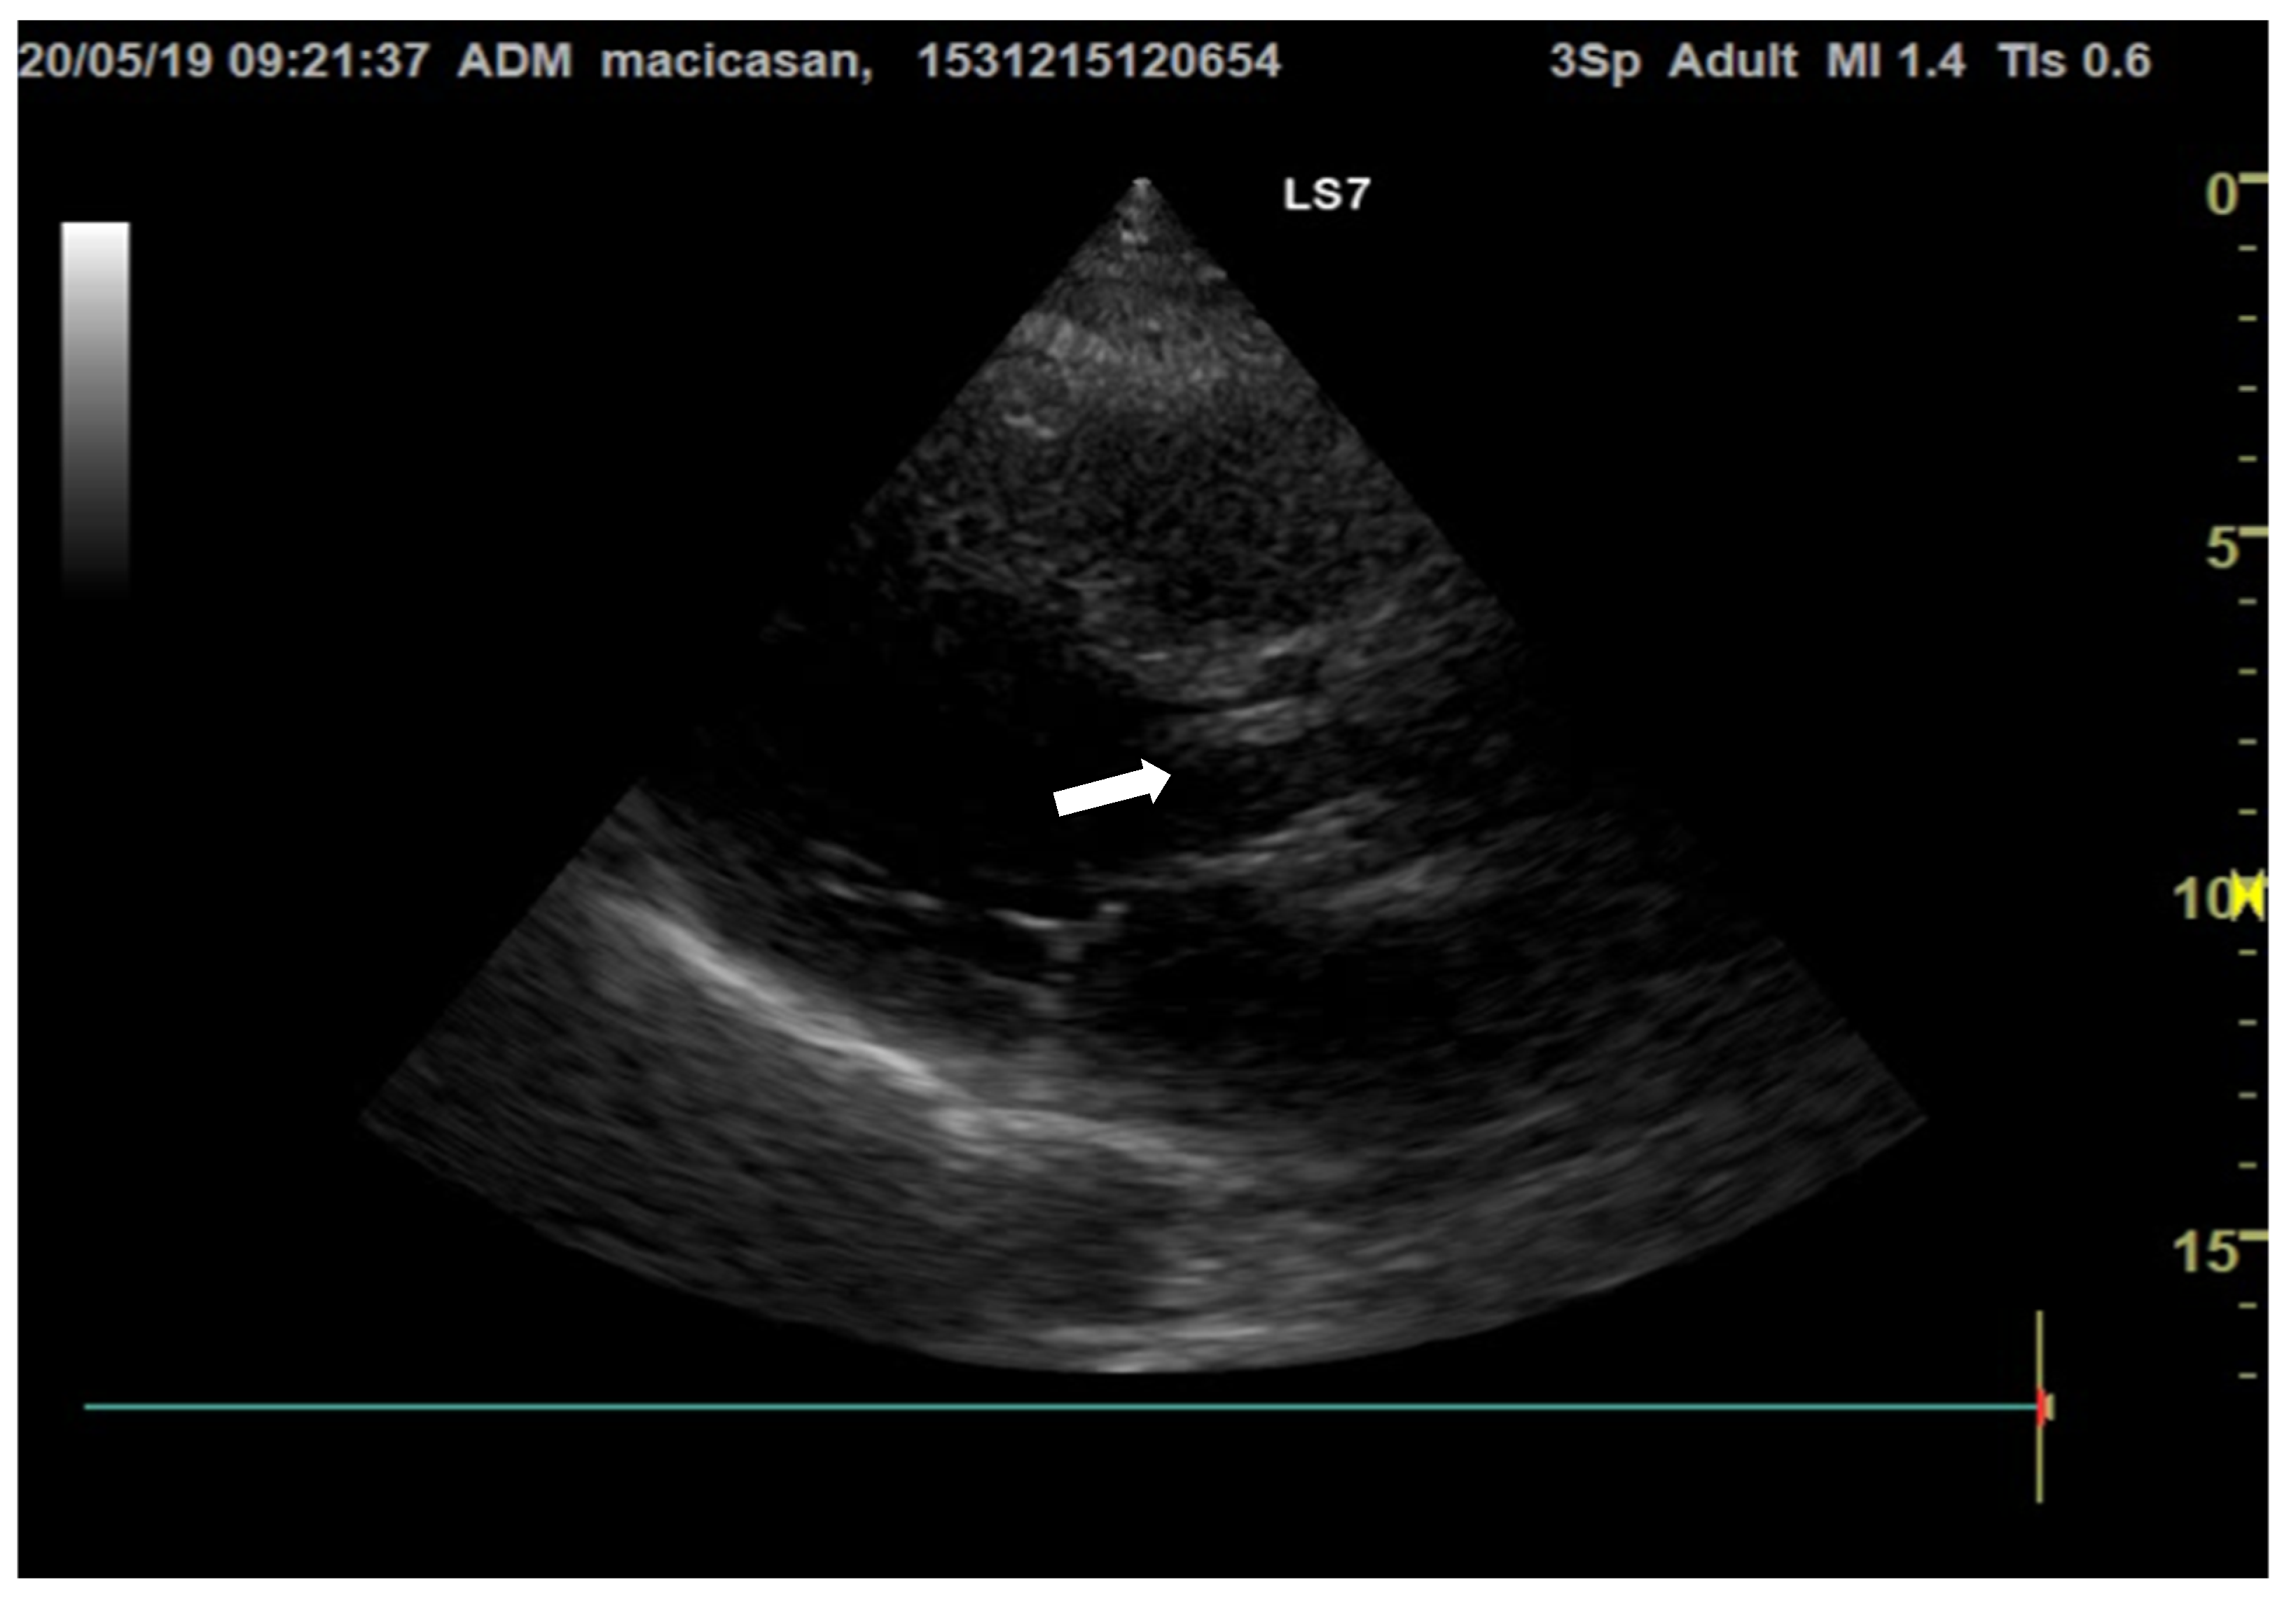

Doppler echocardiography showed a non-dilated left ventricle (LV—55/47 mm), grade III aortic insufficiency with a jet that hit the anterior mitral valve, mobile hyperechoic mass located on the aortic valve (3.5/0.95 cm) and on the tricuspid valve (2.5/1.4 cm), grade II tricuspid insufficiency, moderate secondary pulmonary hypertension (PAPs—50 mmHg), a slightly dilated right ventricle (40 mm sub tricuspid), TAPSE of 22 mm, EF of 50%, and free pericardium (Figure 2 and Figure 3).

Figure 2.

Transthoracic echocardiography, apical 4-chamber view, reveals hyperechogenic vegetations on the tricuspid valve (the white arrow is indicating the vegetation on the aortic valve).